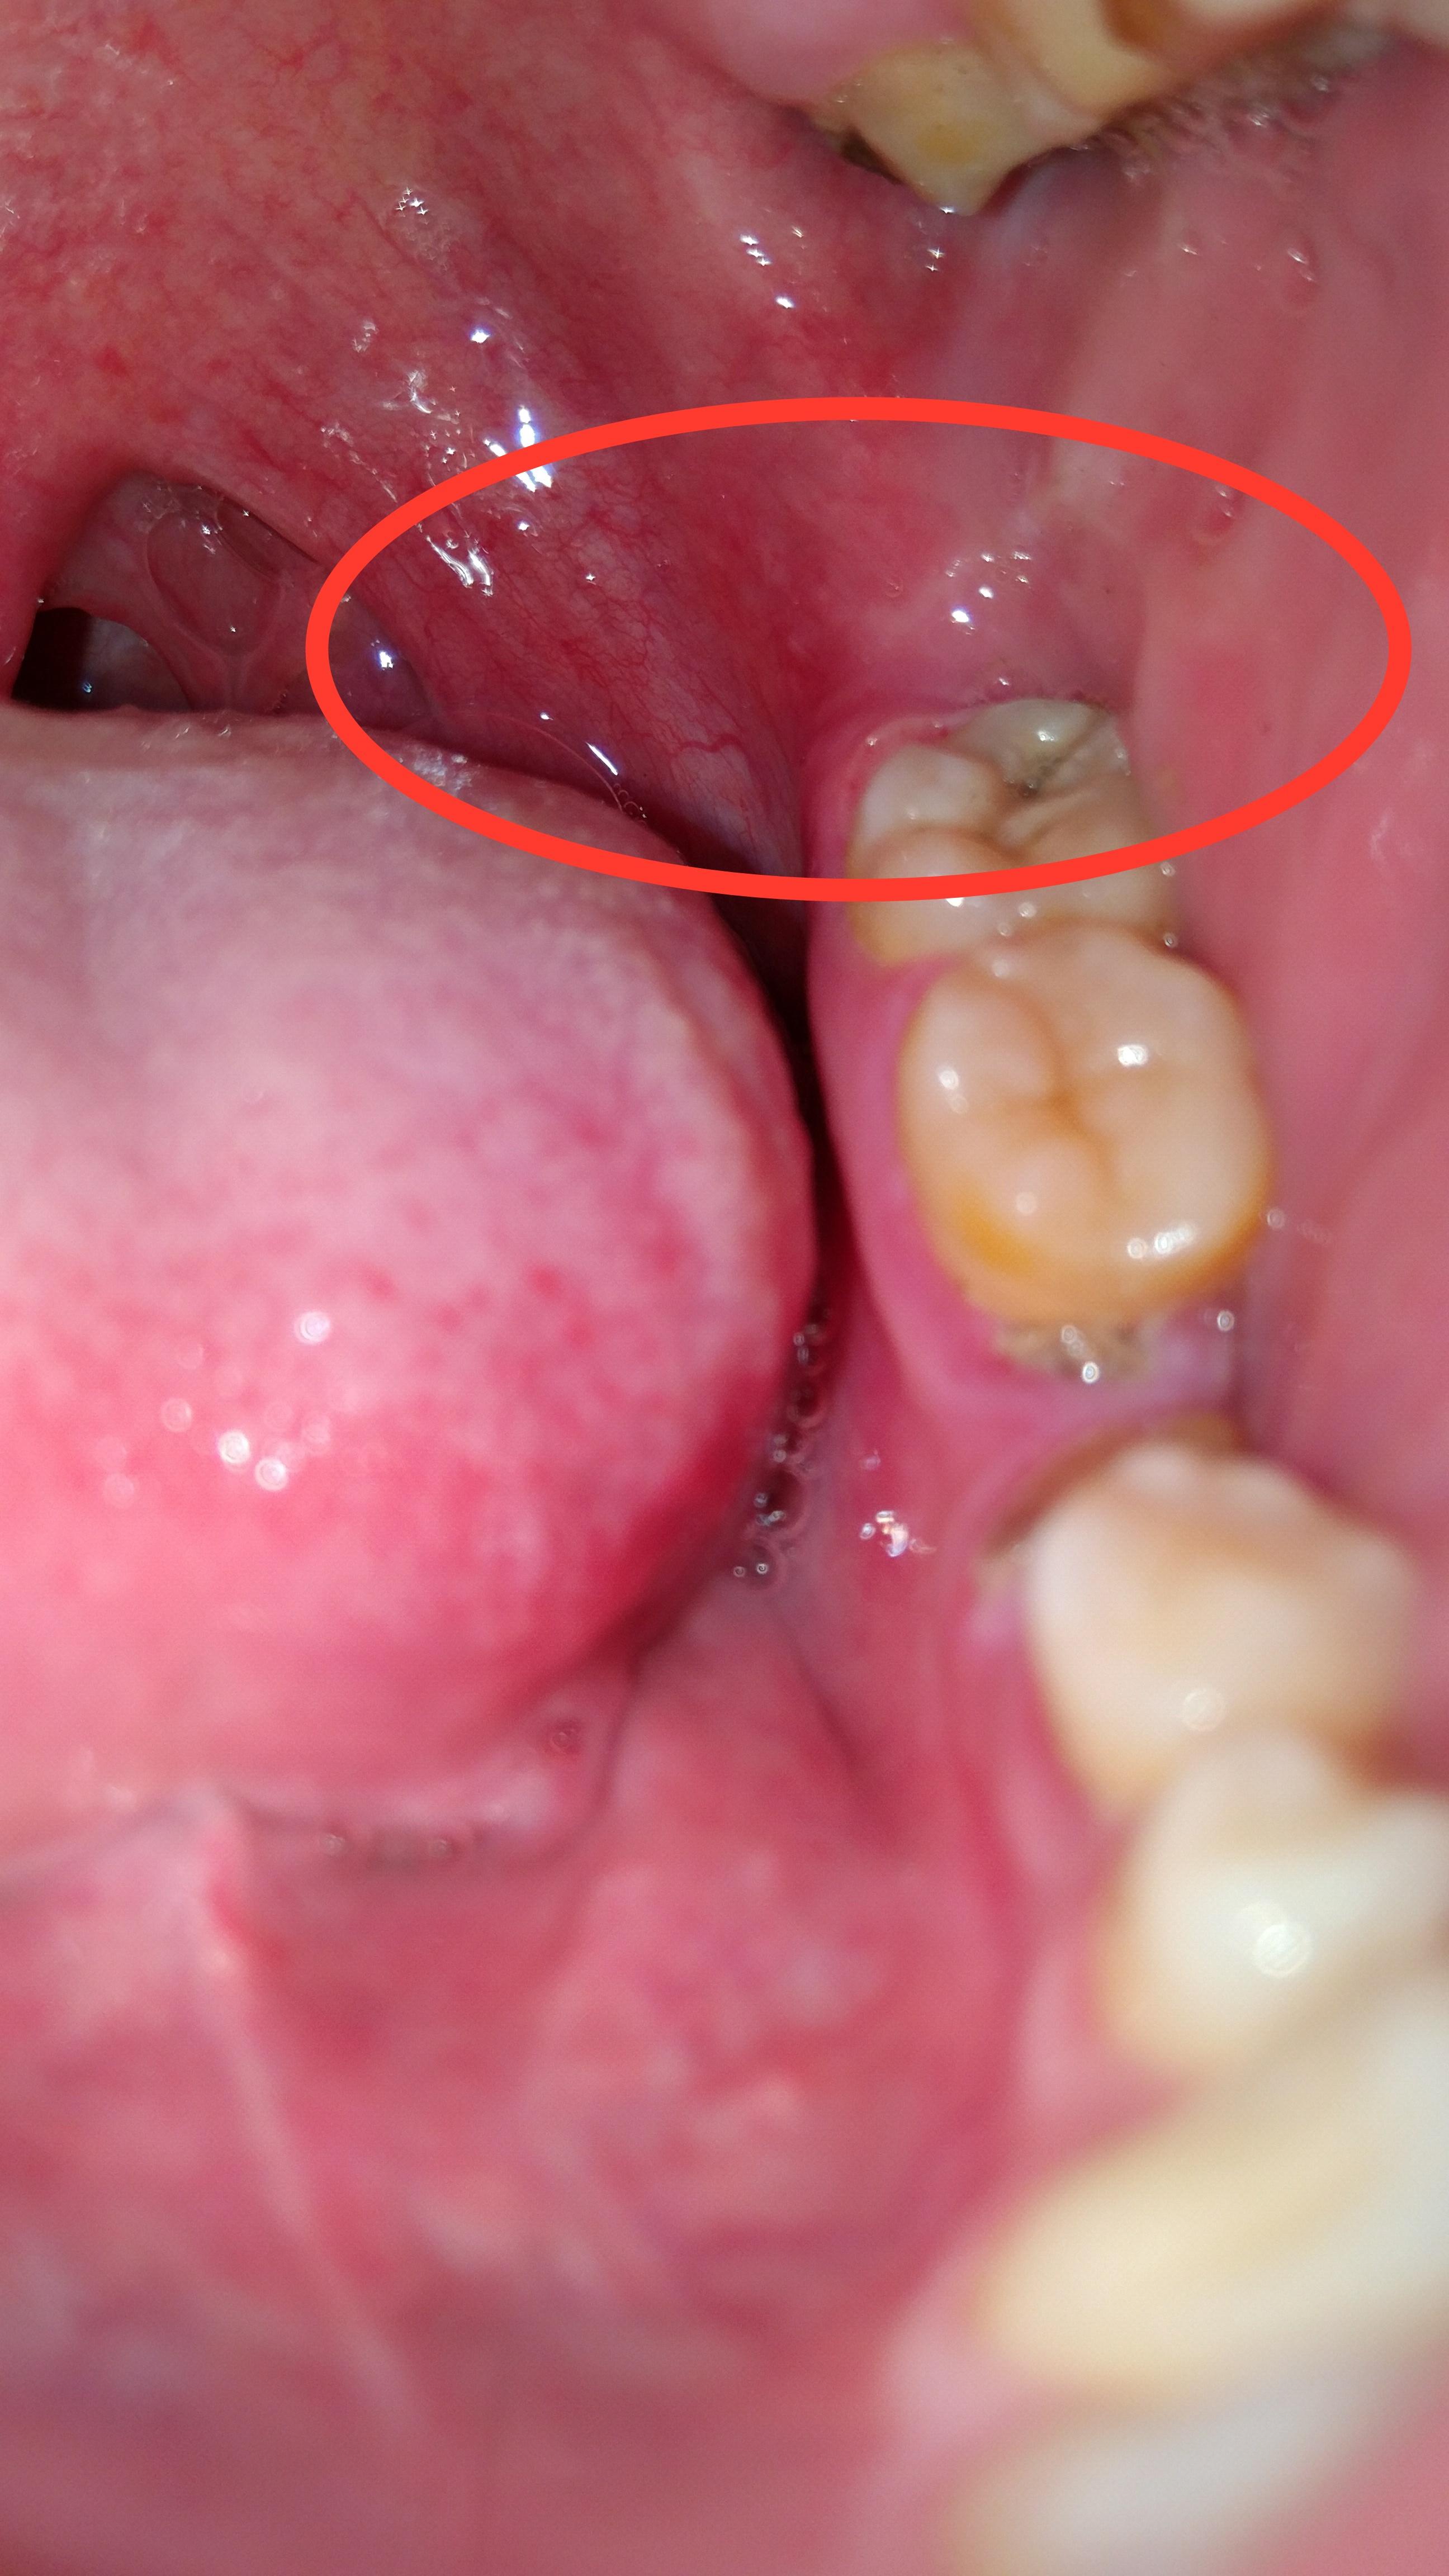

这是智齿冠周炎吗?

最开始左边牙齿最里面的那一颗有些不舒服,而后牙齿周边发疼,现在最里面的肉都非常疼,动嘴就疼。用药酒点了一下,更疼,舌头舔到好像起褶起

用手机开闪光灯拍了一下牙齿。图一图二,这样是智齿冠周炎吗?